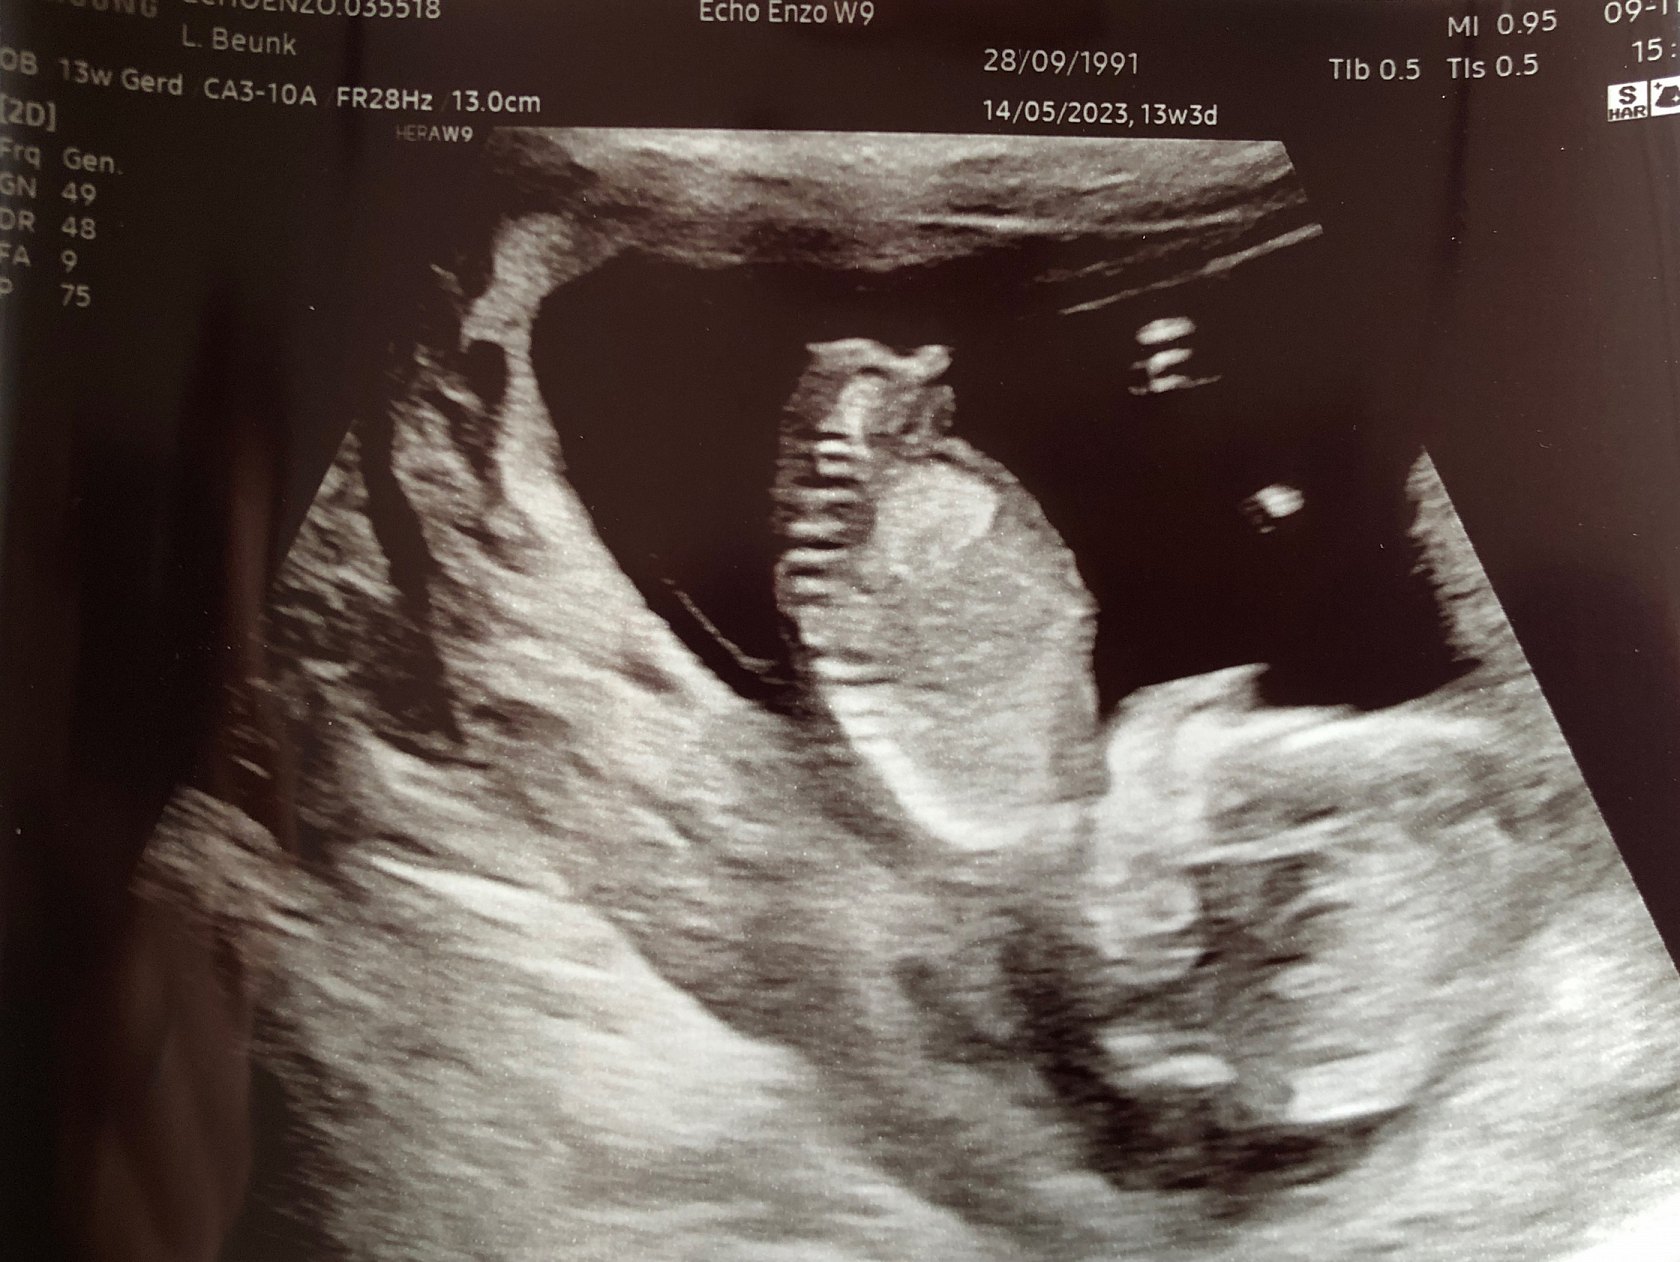

De 13-weken echo

Ook hier zijn alle metingen goed. Een mooi hartje met 4 kamers, 2 niertjes, 2 armpjes, 2 beentjes, 2 hersenhelften, 1 maagje, 1 blaas en een mooie nekplooi.. alles is helemaal goed!